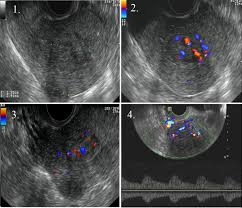

Pentru a diferenția un leiomiom intracavitar de un polip endometrial poate fi folosită examinarea Doppler color unde, nodulii fibromatoși au un model vascular caracteristic- vascularizație marginală din care doar câteva vase pătrund în centrul tumorii. Tot cu ocazia examinării ecografice se poate stabili modul în care nodulii intracavitari sunt atașați la peretele uterin. Aceștia pot prezenta un pedicul subțiere de atașare sau pot avea bază largă de implantare și pot pătrunde în grosimea peretelui uterin. Nodulii intracavitari pediculați pot produce simptome precum crampe abdominale sau durere acută pe măsură ce aceștia pot descinde prin canalul cervical.